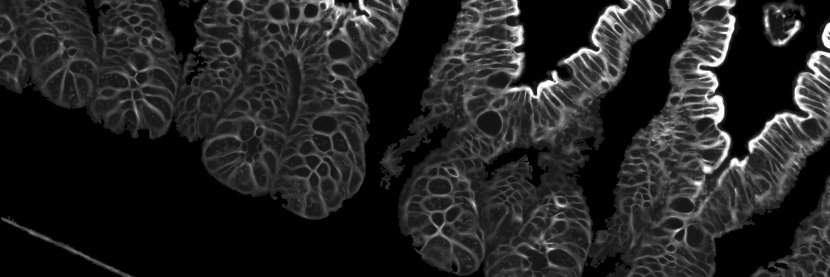

Excited to share our latest work published in @Nature, by grad student @mirazul302, currently on the job market. We uncovered clonal dynamics relating normal to tumor cells using natural and synthetic genetic changes. #SingleCell #DevBio #CRISPR #CRC #HTAN nature.com/articles/s4158…